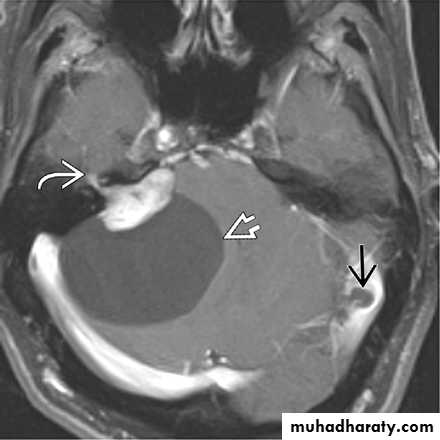

Cerebellopontine angle arachnoid cyst

Investigations:

CT Brain

MRI Brain